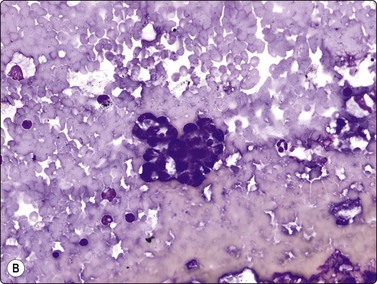

image image

Fig. 11.5 Pancreatic pseudocyst

(A) Mainly debris, inflammatory cells and macrophages; a few clusters of degenerating epithelial cells (Pap, IP); (B) These degenerating epithelial cells may be interpreted as atypical and are a pitfall leading to false-positive diagnoses (MGG, HP).